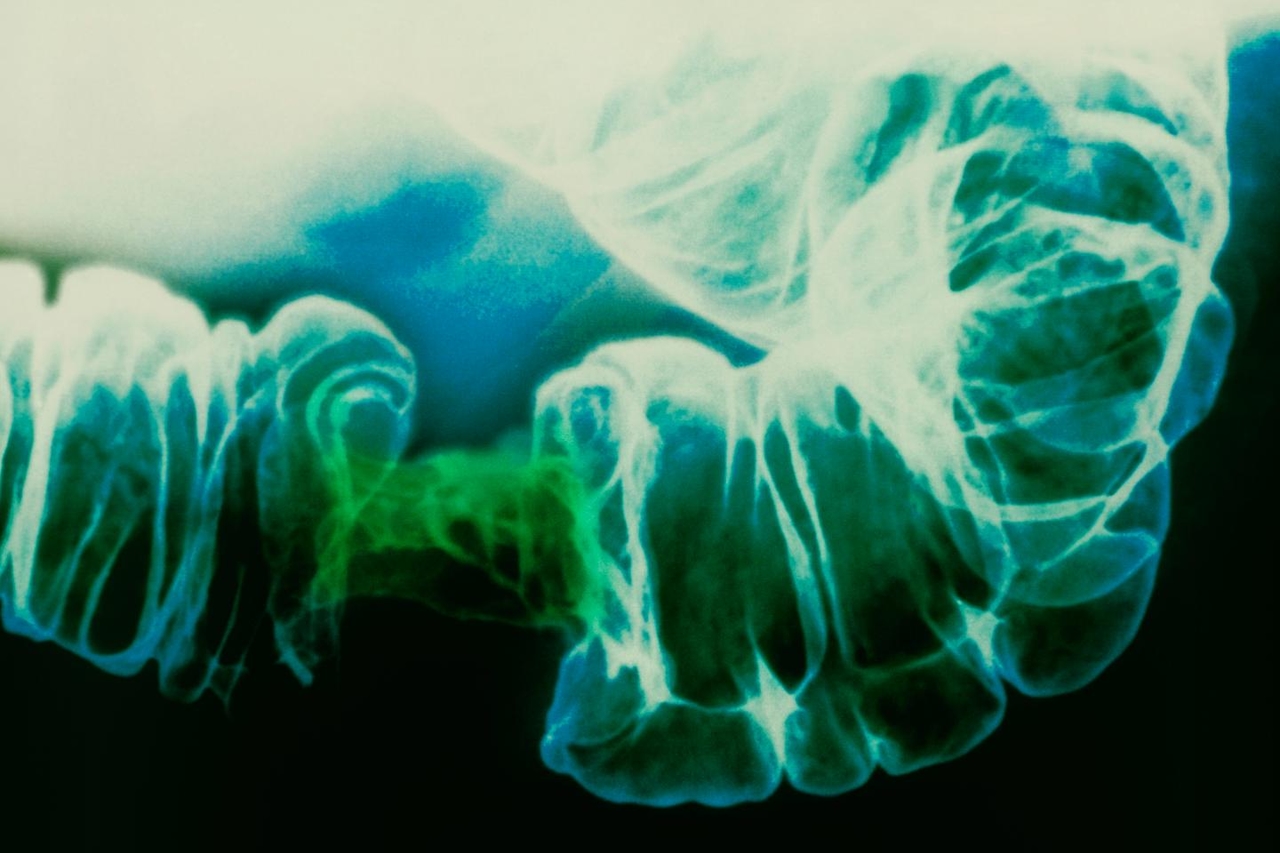

Toutes formes confondues, le cancer colorectal, qui regroupe les cancers du côlon et du rectum, est la troisième cause de cancer dans le monde, avec 1,9 million de personnes diagnostiquées chaque année. Son impact en France est également très important, puisqu’il touche près de 50 000 nouveaux patients par an et représente la deuxième cause de décès par cancer, soit plus de 17 000 morts chaque année.